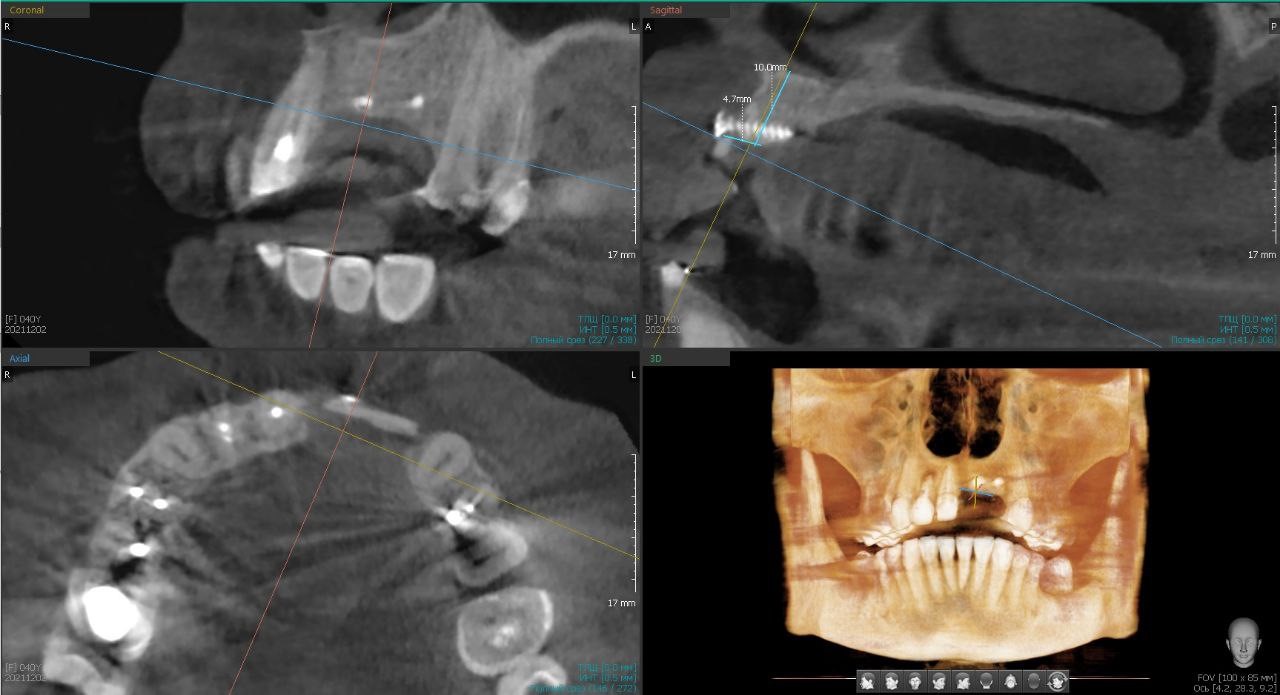

Сама операция проходит примерно так: сначала мы делаем 3D-модель челюсти пациента и распечатываем её на 3D-принтере. На этом куске пластмассы мы предварительно проходим все этапы, в том числе делаем из титановой сетки каркас, «отжимаем» его, формируем ровную конструкцию той формы, которая необходима.

На такой распечатанной на 3D-принтере челюсти мы формируем каркас из титановой сетки и прогоняем все этапы операции

Этот этап очень важен: он позволяет приготовиться к возможным сюрпризам в спокойной обстановке, а не «отбиваться», когда пациент уже второй час сидит с открытым ртом. К тому же подготовка здорово сокращает время операции: вскрываем десну, отслаиваем от кости, наполняем заранее сформированный каркас костной смесью, крепим его к челюсти и ушиваем сверху десну.